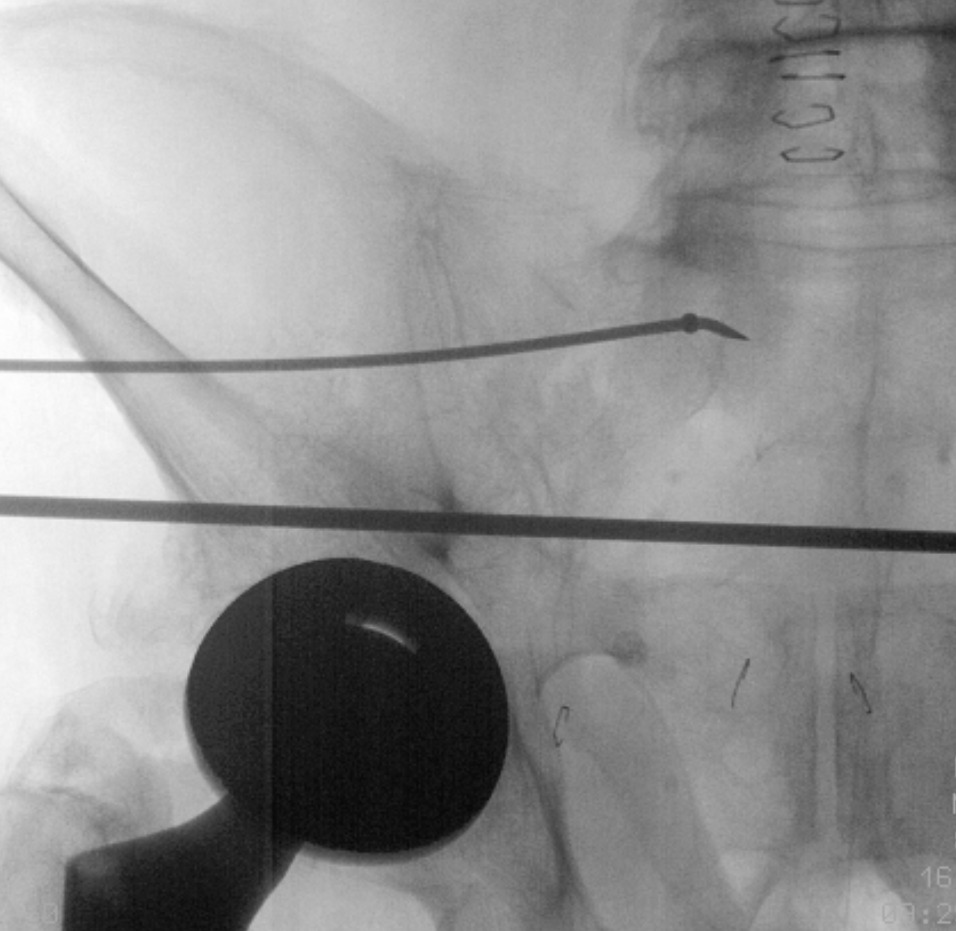

While holding the drill sleeve in place, the 2.8mm guide pin and drill are removed and a steerable guidewire and guide sleeve are inserted into the entry hole. A T-handled chuck is fastened over the guidewire and a mallet is used to tap the guidewire into the desired trajectory, using the ball tip of the guidewire to steer an intraosseous path. The trajectory is checked frequently using inlet and outlet views to confirm the anterior/posterior and cranial/caudal location of the wire. The wire is tapped in until it crosses the opposite SI joint, noting that a fair amount of resistance is met while crossing the SI joint.

Once the guidewire is in position, a depth gauge/implant selection device (ISD) is used to measure the desired length of the flexible intramedullary implant. Next, the guide sleeve is removed while maintaining the drill sleeve. A reamer is advanced over the guidewire, stopping short of the end of the guidewire to maximize purchase in bone. The reamer is removed, and a countersink is used as needed.

An exchange tube is placed over the steerable guidewire fully through the intraosseous channel (Figure 2). The guidewire is removed while making sure the exchange tube remains in place. A 1.6mm driving guidewire is inserted into the exchange tube. The exchange tube is then removed.